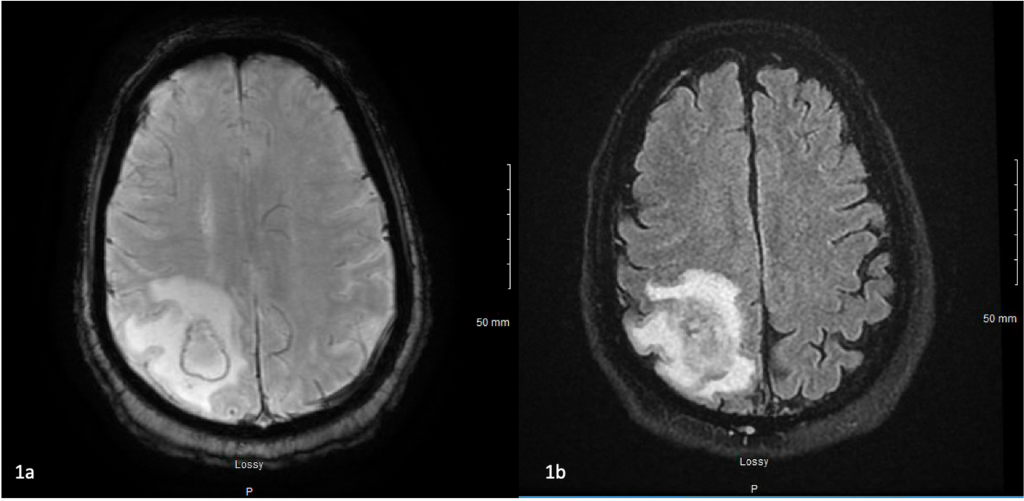

Në varësi të zonës së trupit, mund të ndihen shqetësime të ndryshme si dhimbje, të përziera, të vjella ose ënjtje, dhe nokardioza në tru mund të çojë në kriza, dhimbje koke ose marramendje.

Meqenëse simptomat e nokardiozës mund të tregojnë ndonjë sëmundje, do të jetë e nevojshme të bëni një seri testesh. Këto përfshijnë rrezet X të mushkërive, bronkoskopinë, biopsitë e mushkërive, trurit ose lëkurës, si dhe ekzaminimet e organeve në të cilat u shfaqën simptomat.